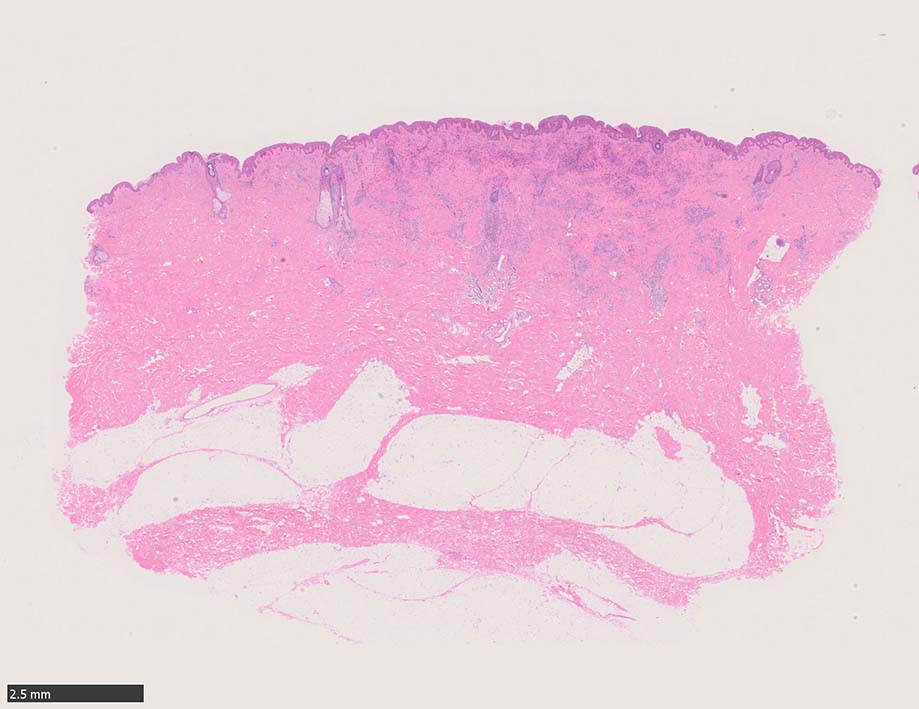

結節性病変の形成

紡錘形細胞が著しく増生し束状に走行する部分と, 内皮細胞様細胞による多数の小管腔構造が巣状にひろがり, 一見, 線維腫と血管腫が混在しているように見える. 一部の症例を除き, これらの増生細胞は異型性に乏しいことが多い.

参考症例:中部交見会1246: Kaposi's sarcoma 右足内側部皮膚/ 40歳代男性 焼津市立病院 久力 権先生